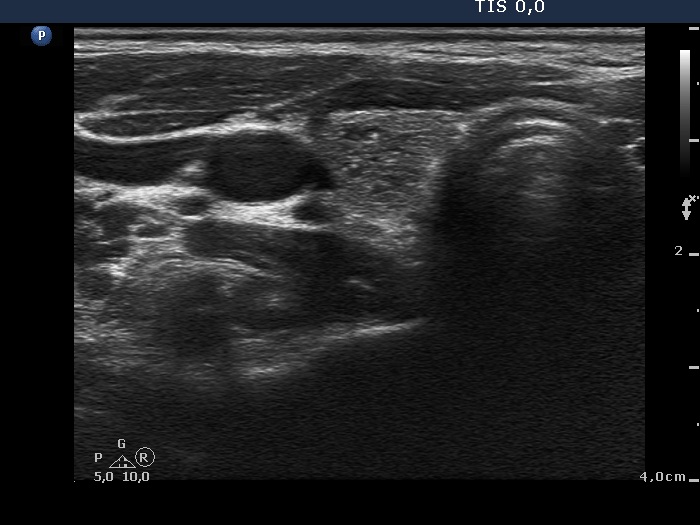

Ultrasonography: The thyroid was echonormal. There was a moderately hypoechogenic inhomogeneous nodule in the lower pole of the right lobe. There were two lymph nodes next to each other above the right thyroid in the submandibular area. The lymph nodes presented a regular hilum.

This is the typical presentation of a bacterially infected lymph node. In most of these cases we find multiple lymph nodes next or very close to each other. The presence of ill-defined hypoechogenic areas within the lymph nodes is an even more important sign of a bacterial lymphadenitis.